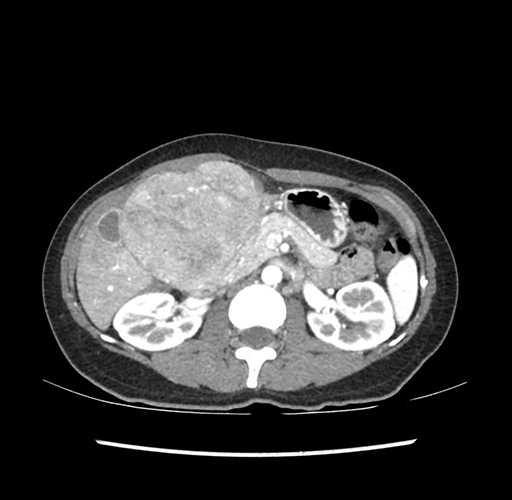

Imaging Analysis

Look through the patient's CT scan to identify any areas of concern for the necessary procedure.

Based on your CT findings, which issue(s) would give reason for "planned slowing down moment(s)" in this case?